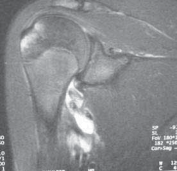

Advanced imaging is non-negotiable in the modern era of instability surgery. Standard radiographic series must include an AP view in internal rotation (to assess for Hill-Sachs lesions and greater tuberosity fractures), a true AP of the glenohumeral joint (Grashey view), and a West Point axillary view to critically evaluate the anteroinferior glenoid rim for bony avulsions or attritional wear. When bony deficiencies are suspected based on plain films or clinical history (e.g., instability during sleep, apprehension at low abduction angles), a 3D reconstructed Computed Tomography (CT) scan with humeral head subtraction is the gold standard. This allows for precise, volumetric quantification of glenoid bone loss utilizing the best-fit circle method. Magnetic Resonance Imaging (MRI), preferably with intra-articular gadolinium arthrography (MRA), is indispensable for evaluating the integrity of the labrum, identifying ALPSA (Anterior Labroligamentous Periosteal Sleeve Avulsion) or GLAD (Glenolabral Articular Disruption) lesions, and ruling out concomitant rotator cuff tears or capsular ruptures.